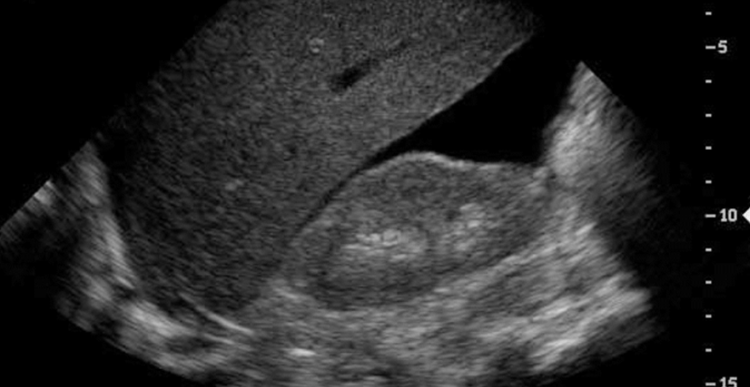

Specialista na zobrazovací metody MVDr. Josef Zatloukal, PhD., povede seminář, jehož cílem je ukázat sílu a význam ultrazvuku v řešení kritických stavů. Absolventi tohoto kurzu si osvojí základní využití echografického zobrazení na živých pacientech.